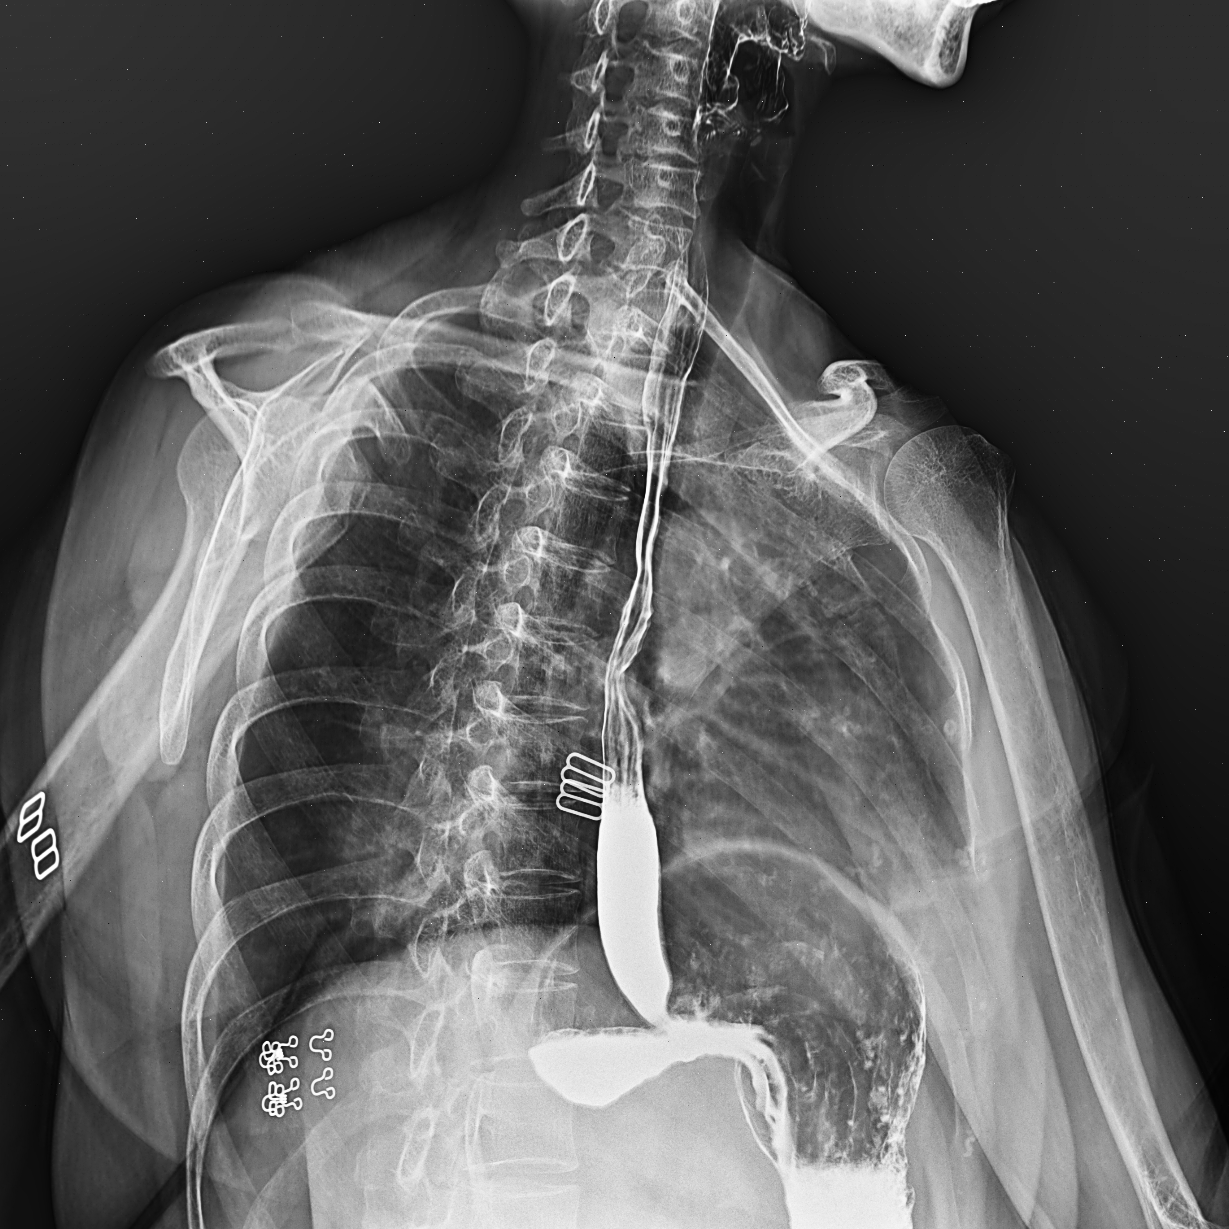

IMG-095351-0001